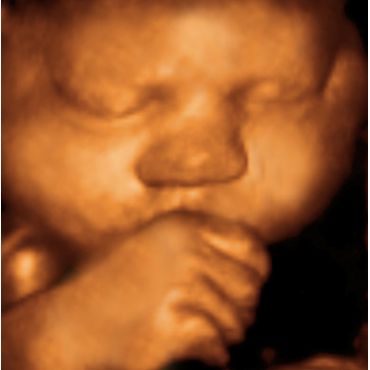

Three-dimensional (3D) Ultrasound is one of this decade's high tech marvels. I produces amazing life-like pictures of your unborn baby. Compared to traditional 2D Ultrasound, 3D shows incredible details and clarity. Real-time, also called 4D Ultrasound, allows you to view your baby's movements inside your womb. The best results are obtained by having your 3D Ultrasound between 20-35 weeks of your pregnancy.

Benefits of 3D/4D Ultrasound allows expectant parets, siblings and family members to have an opportunity to witness the miracle of life and begin instantly bonding with the unborn baby. Parents cherish this unforgettable experience because it amplifies the beauty of pregnancy and creates heightened excitement around the birth of the baby. Research shows that mothers who experience 3D Ultrasound feel more connected to their unborn babies. They also tend to take medical advice more seriously, which in turn improves healthy outcomes for both mother and baby.